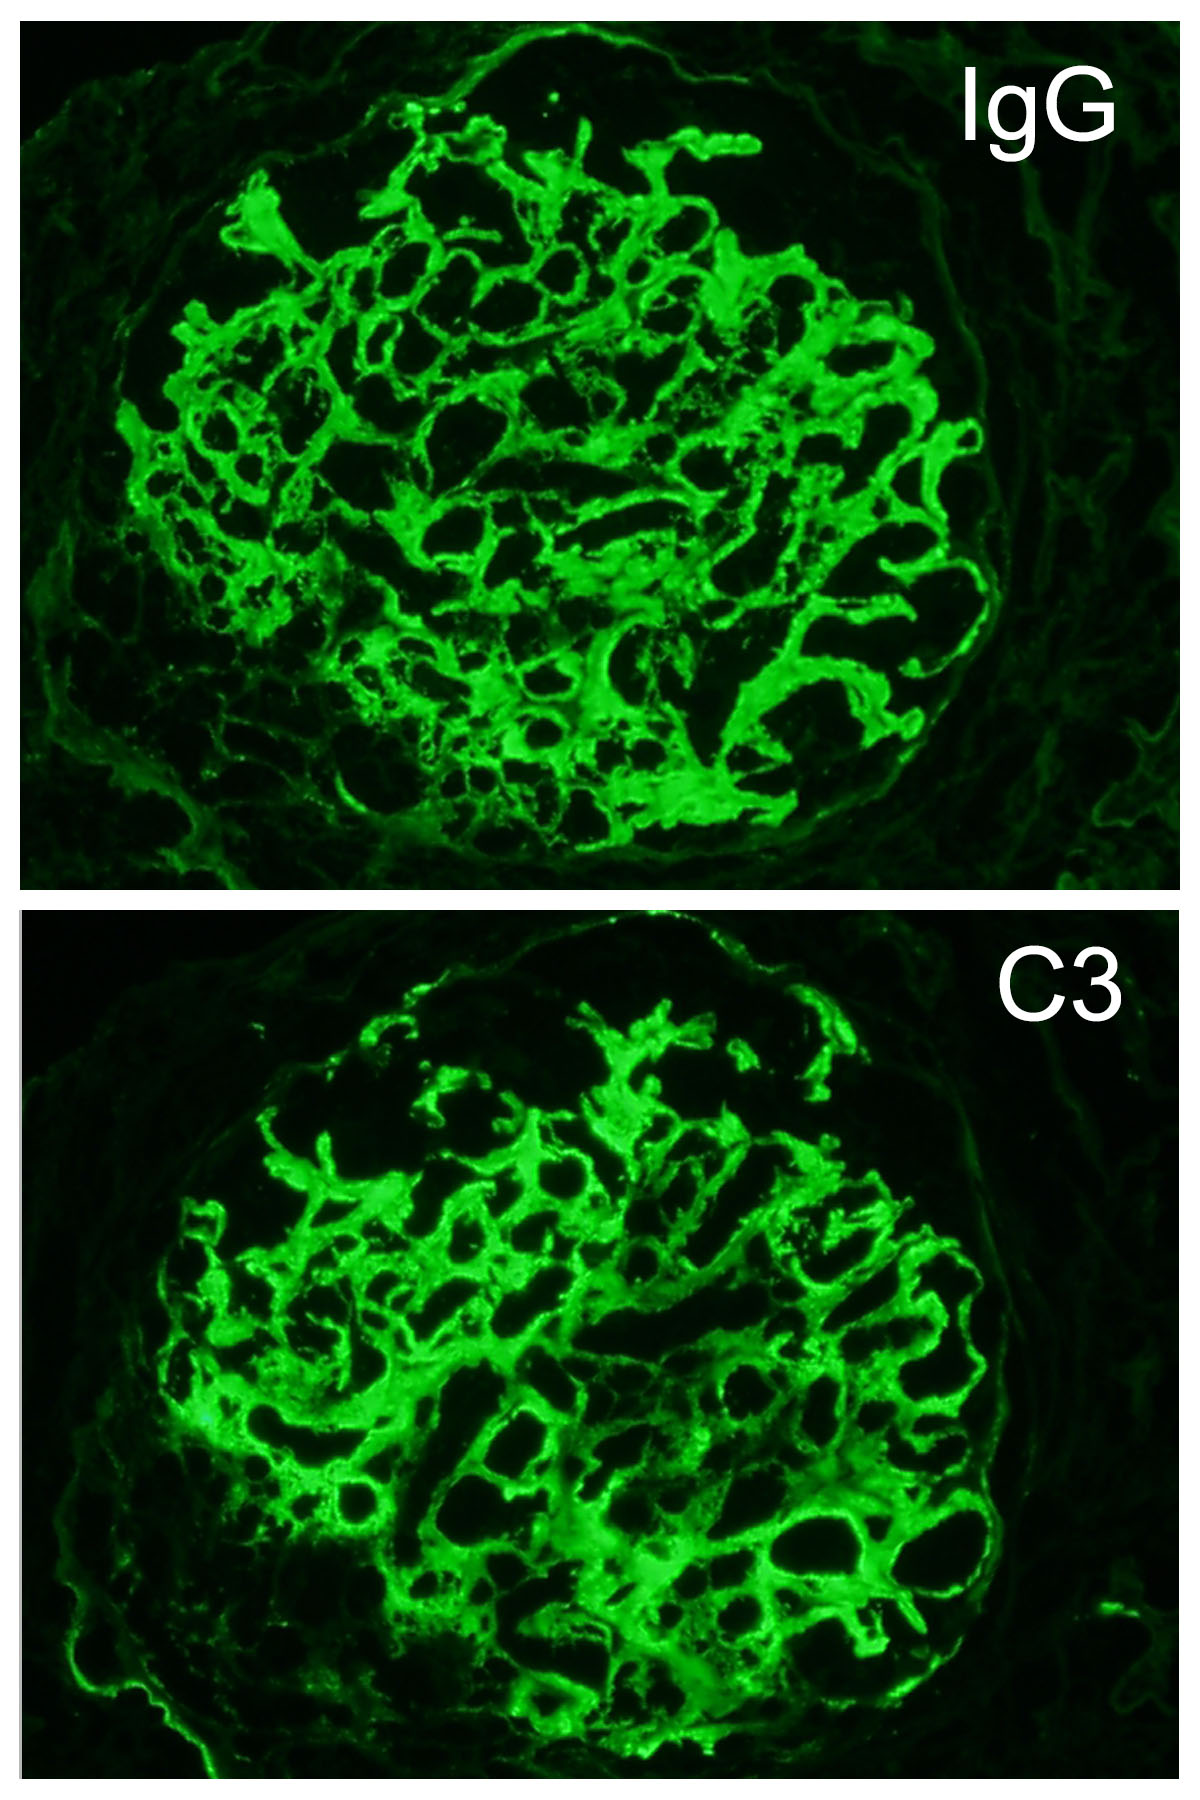

The patient is 32 year-old female with acute kidney injury and nephrotic range proteinuria. A renal biopsy showed diffuse global mesangial and capillary wall expansion by eosinophilic weakly PASH positive material (Silver stain showed in Figure 1), with cellular crescents in 40% and fibrocellular crescents in 5% of the glomeruli. A Congo red stain failed to show apple-green birefringence under polarized light (Figure 2). There was intense immunofluorescence staining with IgG, IgA, C3, and light chains (Figure 3). Electron microscopy showed fibrils with 25 nm average diameter (Figure 4).

By light microscopy, the most commonly reported patterns of injury are membranoproliferative and mesangial proliferative, with focal crescents in 17-50% of the cases (like in this case which showed less than 50% of glomeruli involved; figure). The deposits result in expansion of the mesangium and/or capillary walls by eosinophilic material that is pale with periodic acid-Schiff, nonargyrophilic, and negative for Congo red. By immunofluorescence, “smudgy” mesangial and/or capillary wall intense staining for IgG (most often IgG4 subclass), usually with C3, kappa and lambda light chains is noted. IgM, IgA and C1q show weaker positive staining in some cases.